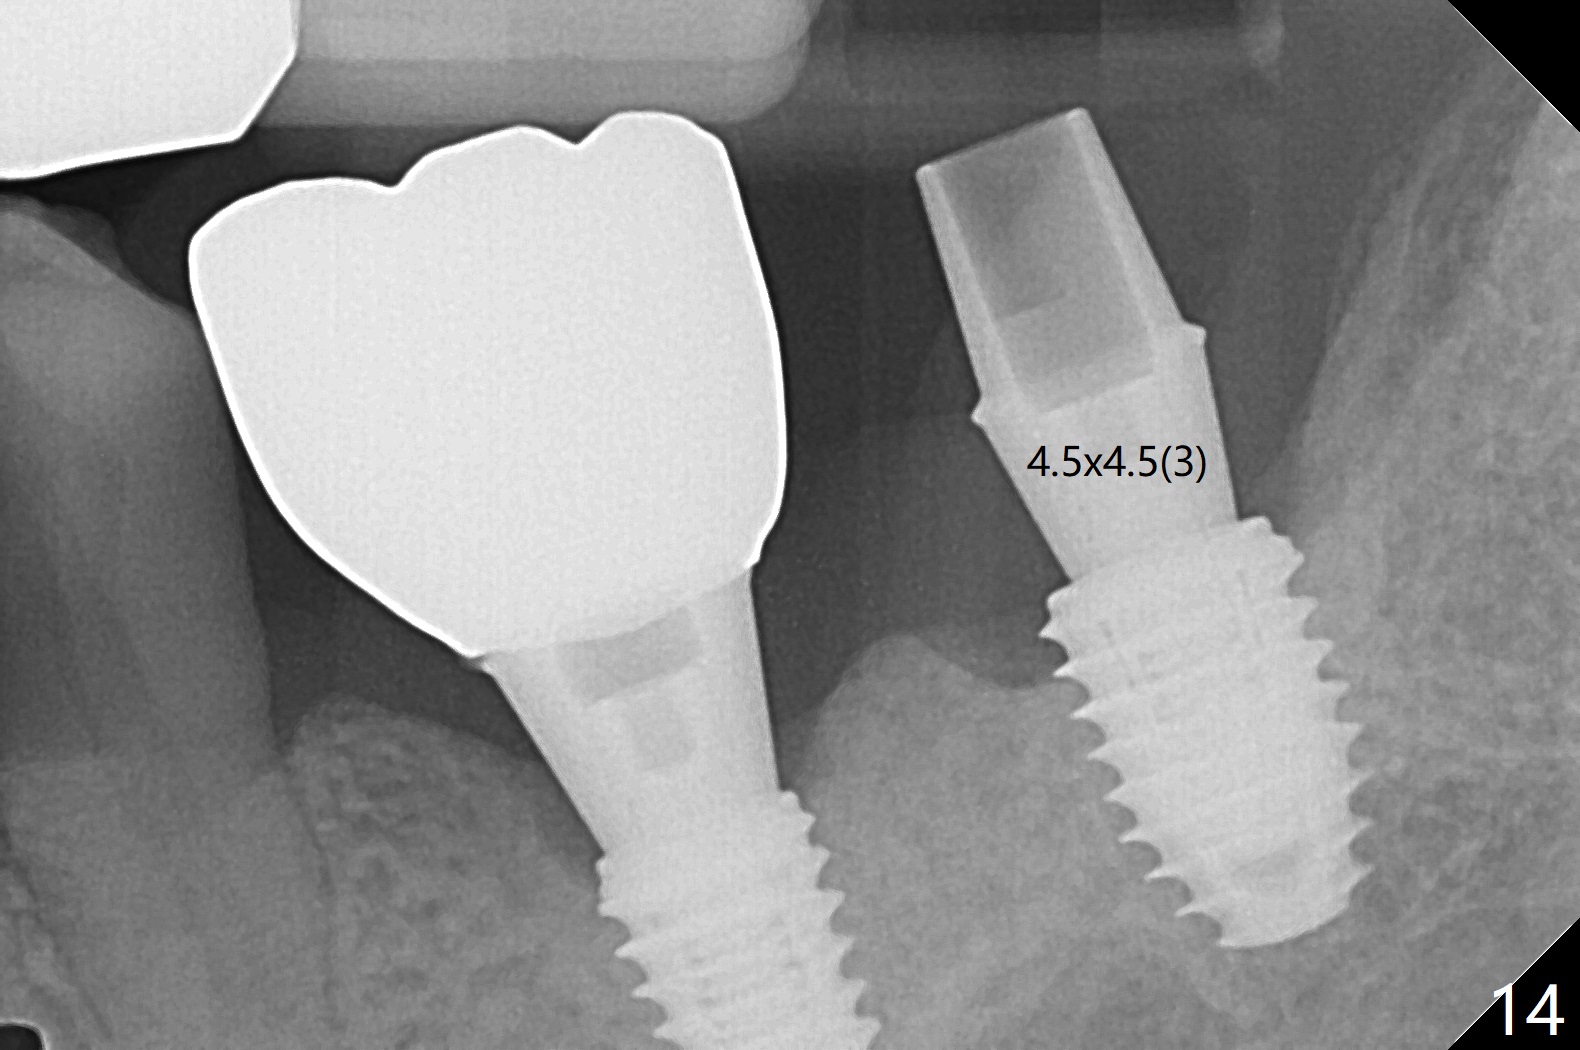

The implants at #12 and 14 are placed 1 month later (Fig.4). The 4 implants have impression (Fig.5,6) and cementation (Fig.7-9) at the same time. Although the upper FPD is able to be removed after cementation in the mouth (Fig.7), the abutment screw cannot be tightened >20 Ncm (Fig.8). The tooth #15 is tender early after crown/FPD cementation and needs occlusal adjustment twice. The crown of #18 dislodges eight months post cementation (Fig.11 taken after recementation). There is no bone loss at #13 and 15 (Fig.10), while the bone density increases around the implants at #18 and 19 eight months post cementation (Fig.11). The abutment screw at #18 become loose 1.5 years post cementation; after proximal surface trimming twice (<), the abutment remains incompletely seated (Fig.12,13). With suspicion of soft tissue block (Fig.13 *), a small abutment with longer cuff is completely seated (Fig.14).